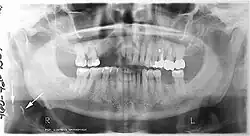

Orthopantomograms (OPTs) are used by health care professionals to provide information on:

- Impacted wisdom teeth diagnosis and treatment planning - the most common use is to determine the status of wisdom teeth and trauma to the jaws.

- Periodontal bone loss and periapical involvement.

- Finding the source of dental pain, and when carrying out tooth-by-tooth diagnosis.

- Assessment for the placement of dental implants

- Orthodontic assessment. pre and post operative

- Diagnosis of developmental anomalies such as cherubism, cleido cranial dysplasia

- Carcinoma in relation to the jaws

- Temporomandibular joint dysfunctions and ankylosis.

- Diagnosis of osteosarcoma, ameloblastoma, renal osteodystrophy affecting jaws and hypophosphatemia.

- Diagnosis, and pre- and post-surgical assessment of oral and maxillofacial trauma, e.g. dentoalveolar fractures and mandibular fractures.

- Salivary stones (Sialolithiasis).

- Other diagnostic and treatment applications.[2]